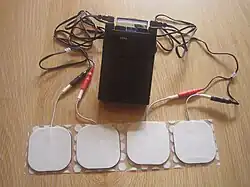

TENS

Die transkutane elektrische Nervenstimulation (TENS) ist die Anwendung von Reizstrom, die in der Zahnmedizin neben der Behandlung von Schmerzen auch zur Analgesie bei kleineren Eingriffen wie beispielsweise der Kariestherapie eingesetzt wird. Als Mechanismen sollen schmerzhemmende Botenstoffe (Neurotransmitter) und Endorphine sowie Enkephaline vermehrt ausgeschüttet werden. Durchblutungsfördernde gefäßerweiternde Substanzen wie beispielsweise vasoaktives intestinales Peptid (VIP-Hormon) werden vermehrt gebildet, wodurch die Übertragung von Schmerzimpulsen blockiert wird. Die Impulsweiterleitung peripherer (außerhalb des Rückenmarks und des Gehirns liegender) Nerven wird durch elektrische Hemmvorgänge blockiert.[31][32]

Das batteriebetriebene TENS-Therapiegerät besteht aus einem Generator und zwei Elektroden. Die Elektroden werden intraoral (im Mund) oder extraoral (außerhalb des Mundes) angebracht. Die Impulsstärke, -frequenz und Stromstärke werden vom Zahnarzt vorab eingestellt, können aber durch den Patienten über einen Handregler je nach Schmerzintensität verändert werden.